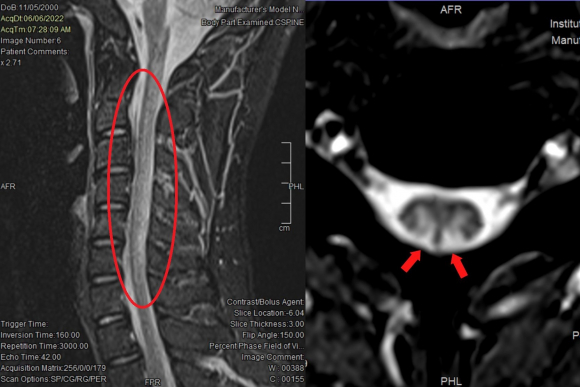

Hình ảnh tổn thương tủy cổ trên phim chụp MRI gợi ý ngộ độc N2O. Ảnh: Bệnh viện cung cấp.

Bác sĩ Thủy cảnh báo, một số người, đặc biệt là giới trẻ có thói quen sử dụng bóng cười vào mục đích giải trí, xả stress trong thời gian dài có thể gây ra hệ lụy nghiêm trọng cho hệ thần kinh. Trong đó, tình trạng thường gặp nhất là tổn thương đa rễ và dây thần kinh, tủy sống (đặc biệt ở vùng cột sau chịu trách nhiệm chức năng thăng bằng). Bệnh nhân có biểu hiện rối loạn cảm giác ở tay chân, dáng đi, mất khả năng điều hòa động tác, tay chân tê yếu, đi lại không vững, đau đầu, đau cổ, nói khó, loạn thần, ảo giác... Tổn thương thường gặp khác là thiếu máu hồng cầu to do thiếu vitamin B12.